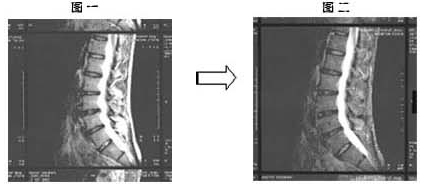

该病患于2002年被诊断出罹患腰椎间盘突出症,2003年3月9日因腰关节痛和坐骨神经痛而到本院接受诊疗。

约一年前因突然腰关节痛和坐骨神经痛导致无法行动,在整型外科诊断出罹患腰椎间盘突出症。之后,接受牵引治疗,服用抗炎药物等治疗方法,但始终未见成效。在那样情况下,该病患只好放弃汽车工厂的工作,办理停职一年。之后,2003年3月到本院接受诊疗,利用MRI(核磁共振图)(参看图一)诊断出腰椎间盘突出症。在确认该病患之前所接受的治疗经过后,得到患者本人同意,开始改以每日服用7.5g 百傲鲨锯峰齿鲛软骨粉末的治疗方式。

一个月后于4月3日接受诊察时,腰关节痛感和坐骨神经痛感已减轻。之后也持续服用,5月1日再次检查时,腰关节痛感已完全消失。同年的10月,从原本无法工作已恢复到一周可出席两次五人制足球赛。服用一年后的现在,也已回到工作岗位,之后也未再出现腰椎间盘突出症和坐骨神经痛的相关症状。

2003年3月初诊时的MRI(核磁共振图)(参看图一)与2004年4月的MRI(核磁共振图)(参看图二)相比,可清楚看到腰椎间盘突出症状,已有明显的改善。

椎间盘的场合,用软骨再生来表达不太合适,但可知软骨已恢复了正常弹性。而且,服用一个月后腰关节痛和坐骨神经痛感减少,两个月后疼痛状况完全消失,由此可得知百傲鲨对腰椎间盘突出症,具有消除坐骨神经痛和腰腿关节痛的效果。